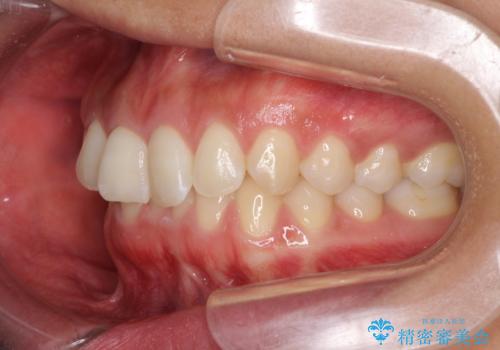

- 深い咬み合わせ(ディープバイト)と前歯のデコボコを気にして来院された患者様です。

インビザラインによる上下歯列の側方拡大と後方移動、IPR(歯と歯の間を削る)にるスペースの獲得により、デコボコとディープバイトを改善することとしました。

1日22時間の装着時間をしっかり守ってくださったので、予定通り1年で治療を終えることができました。

ディープバイトによる食いしばり癖も解消され、患者様には大変満足していただきました。